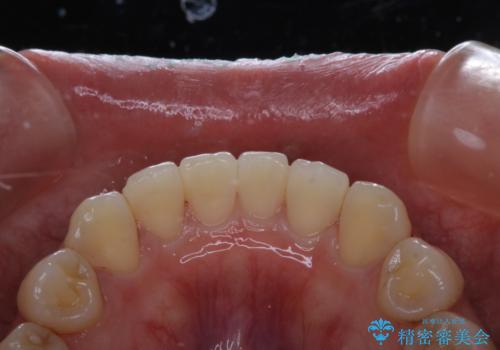

前歯のセラミック製作前にPMTC

- 前歯のすき間をセラミックで治療するため、処置前にクリーニングを希望されました。PMTC30分コースを行いました。

PMTCは、国家資格取得者の歯科衛生士により、専門的な機械や材料を使用してのクリーニングです。一人一人の患者様のお口の状態に合わせたクリーニングを行います。

セラミック治療などの際に歯肉が腫れていたり、治療中に出血したりすると

、精密に型取りができなかったりすることがあります。

PMTCを行うことで、歯肉の引き締まりも期待できます。治療前にもPMTCを行うことはおすすめです。